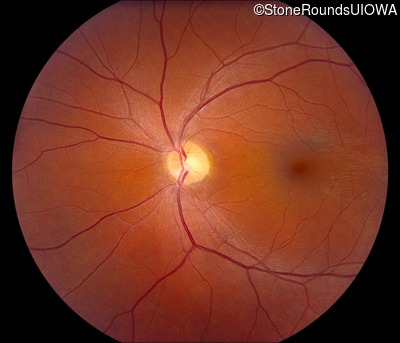

Congenital Stationary Synaptic Dysfunction (IA2g)

Congenital Stationary Synaptic Dysfunction (IA2g)

Diagnosis & molecular findings

| Disease | Gene | Allele 1 variant(s) | Allele 2 variant(s) | Inheritance mode |

|---|---|---|---|---|

| Congenital Stationary Synaptic Dysfunction | CABP4 | Arg49Stop CGA>TGA | IVS1+1 G>T | AR |